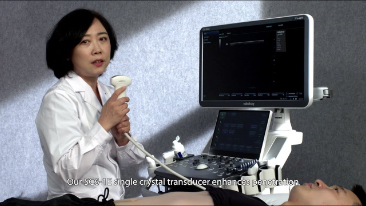

La gamme d'imagerie gÊnÊrale Resona de Mindray aide les cliniciens à obtenir des rÊsultats de diagnostic plus prÊcis et des traitements plus efficaces gr?ce à une gamme de sondes complète et à des outils cliniques avancÊs efficaces.